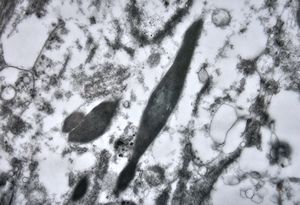

bone marrow - crystalloid inclusions Charcot-Leyden crystals formation

bone marrow - crystalloid inclusions Charcot-Leyden crystals formation v.s.